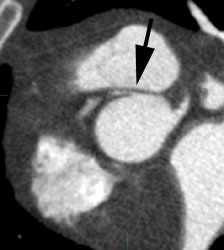

2- Myocardium- in the post-prandial state, there is marked cardiac activity. Little myocardial activity is generally noted in the fasting state as the myocardium preferentially utilizes fatty acids for energy generation. However, uptake can be variable as even in the fasting state, glucose can still account for 30-40% of the energy derived from oxidative metabolism [25]. Increased FDG uptake has also been reported in lipomatous hypertrophy of the interatrial septum- mean SUV 5.6 [101]. Uptake can be seen in up to 82% of patients with LHIS [101]. The etiology for the uptake is not certain, but may be related to the presence of brown fat [101]. Fusion PET/CT helps to clarify the location of the uptake [101].